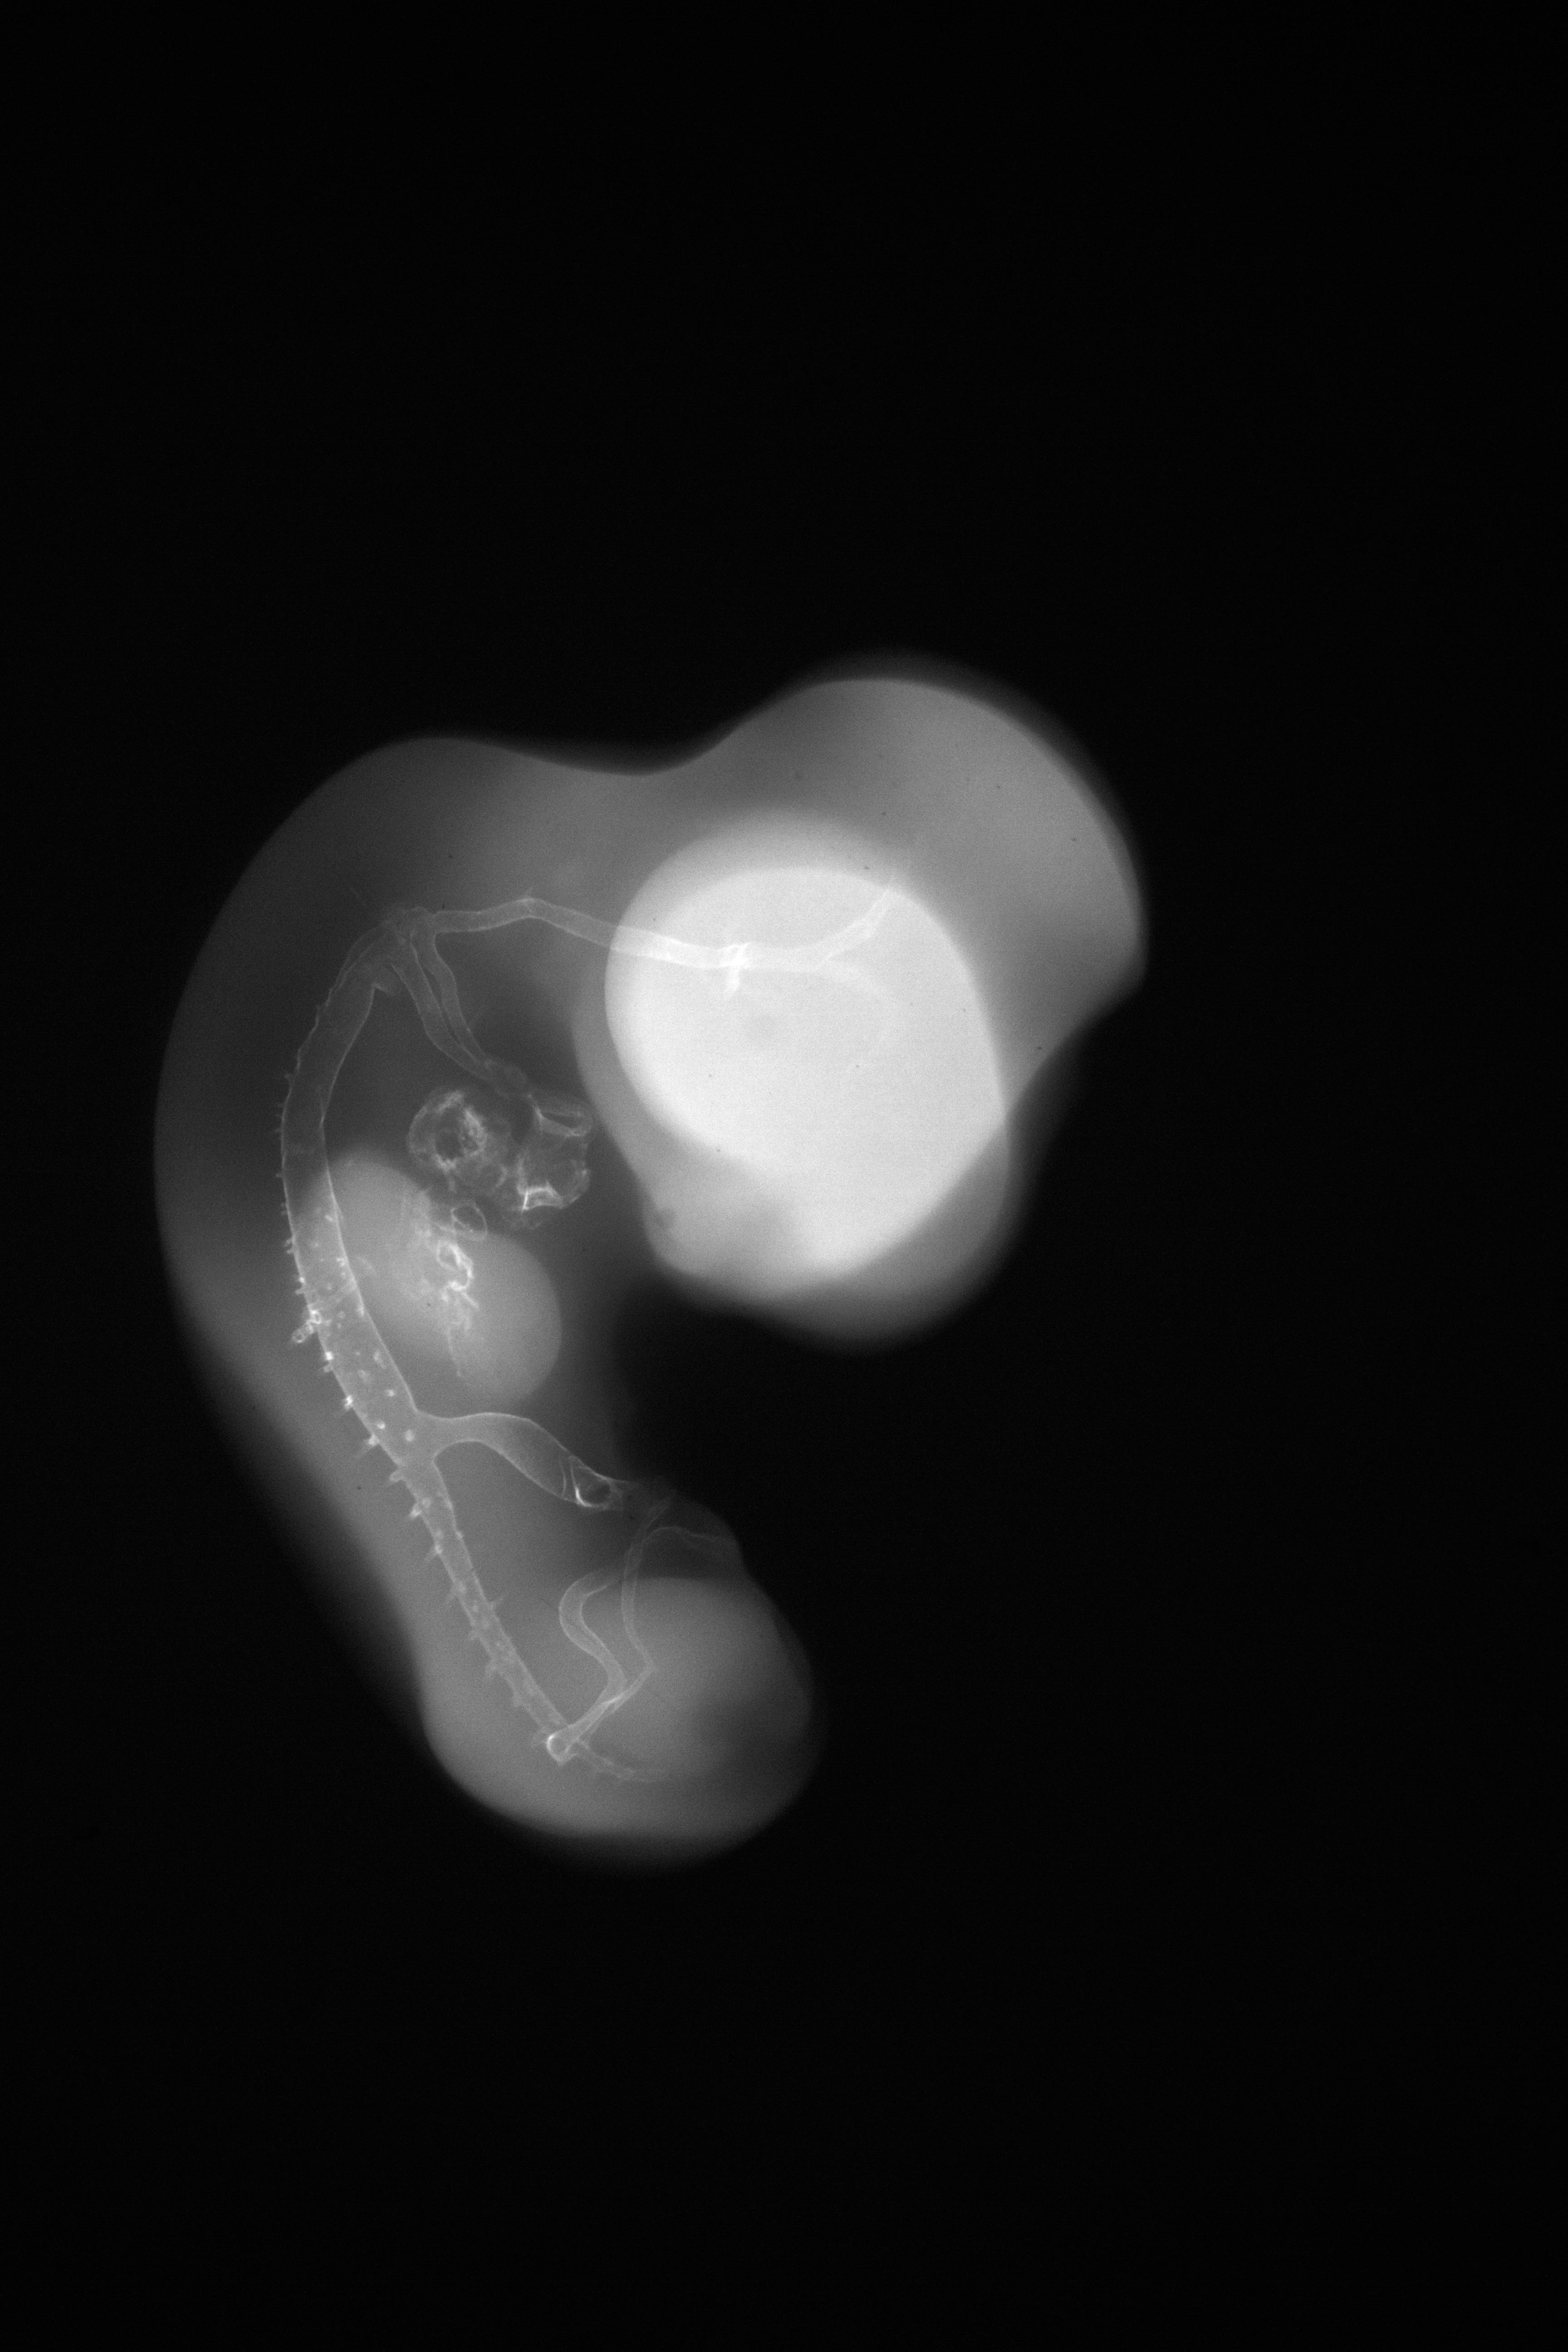

Chick Embryo Microangiography

Hamburger-Hamilton (HH) Stage 27 (approx. 5 - 5.5 days)

X-Ray Micrographs